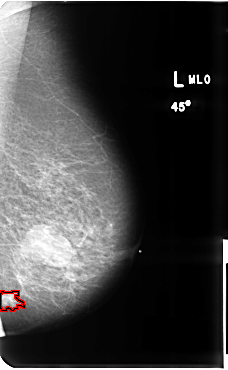

B_3512_1.LEFT_MLO

FILE: B_3512_1.LEFT_MLO.OVERLAY

TOTAL_ABNORMALITIES 1

ABNORMALITY 1

LESION_TYPE CALCIFICATION TYPE PLEOMORPHIC DISTRIBUTION CLUSTERED

LESION_TYPE MASS SHAPE IRREGULAR-ARCHITECTURAL_DISTORTION MARGINS SPICULATED

ASSESSMENT 5

SUBTLETY 4

PATHOLOGY MALIGNANT

TOTAL_OUTLINES 1

BOUNDARY